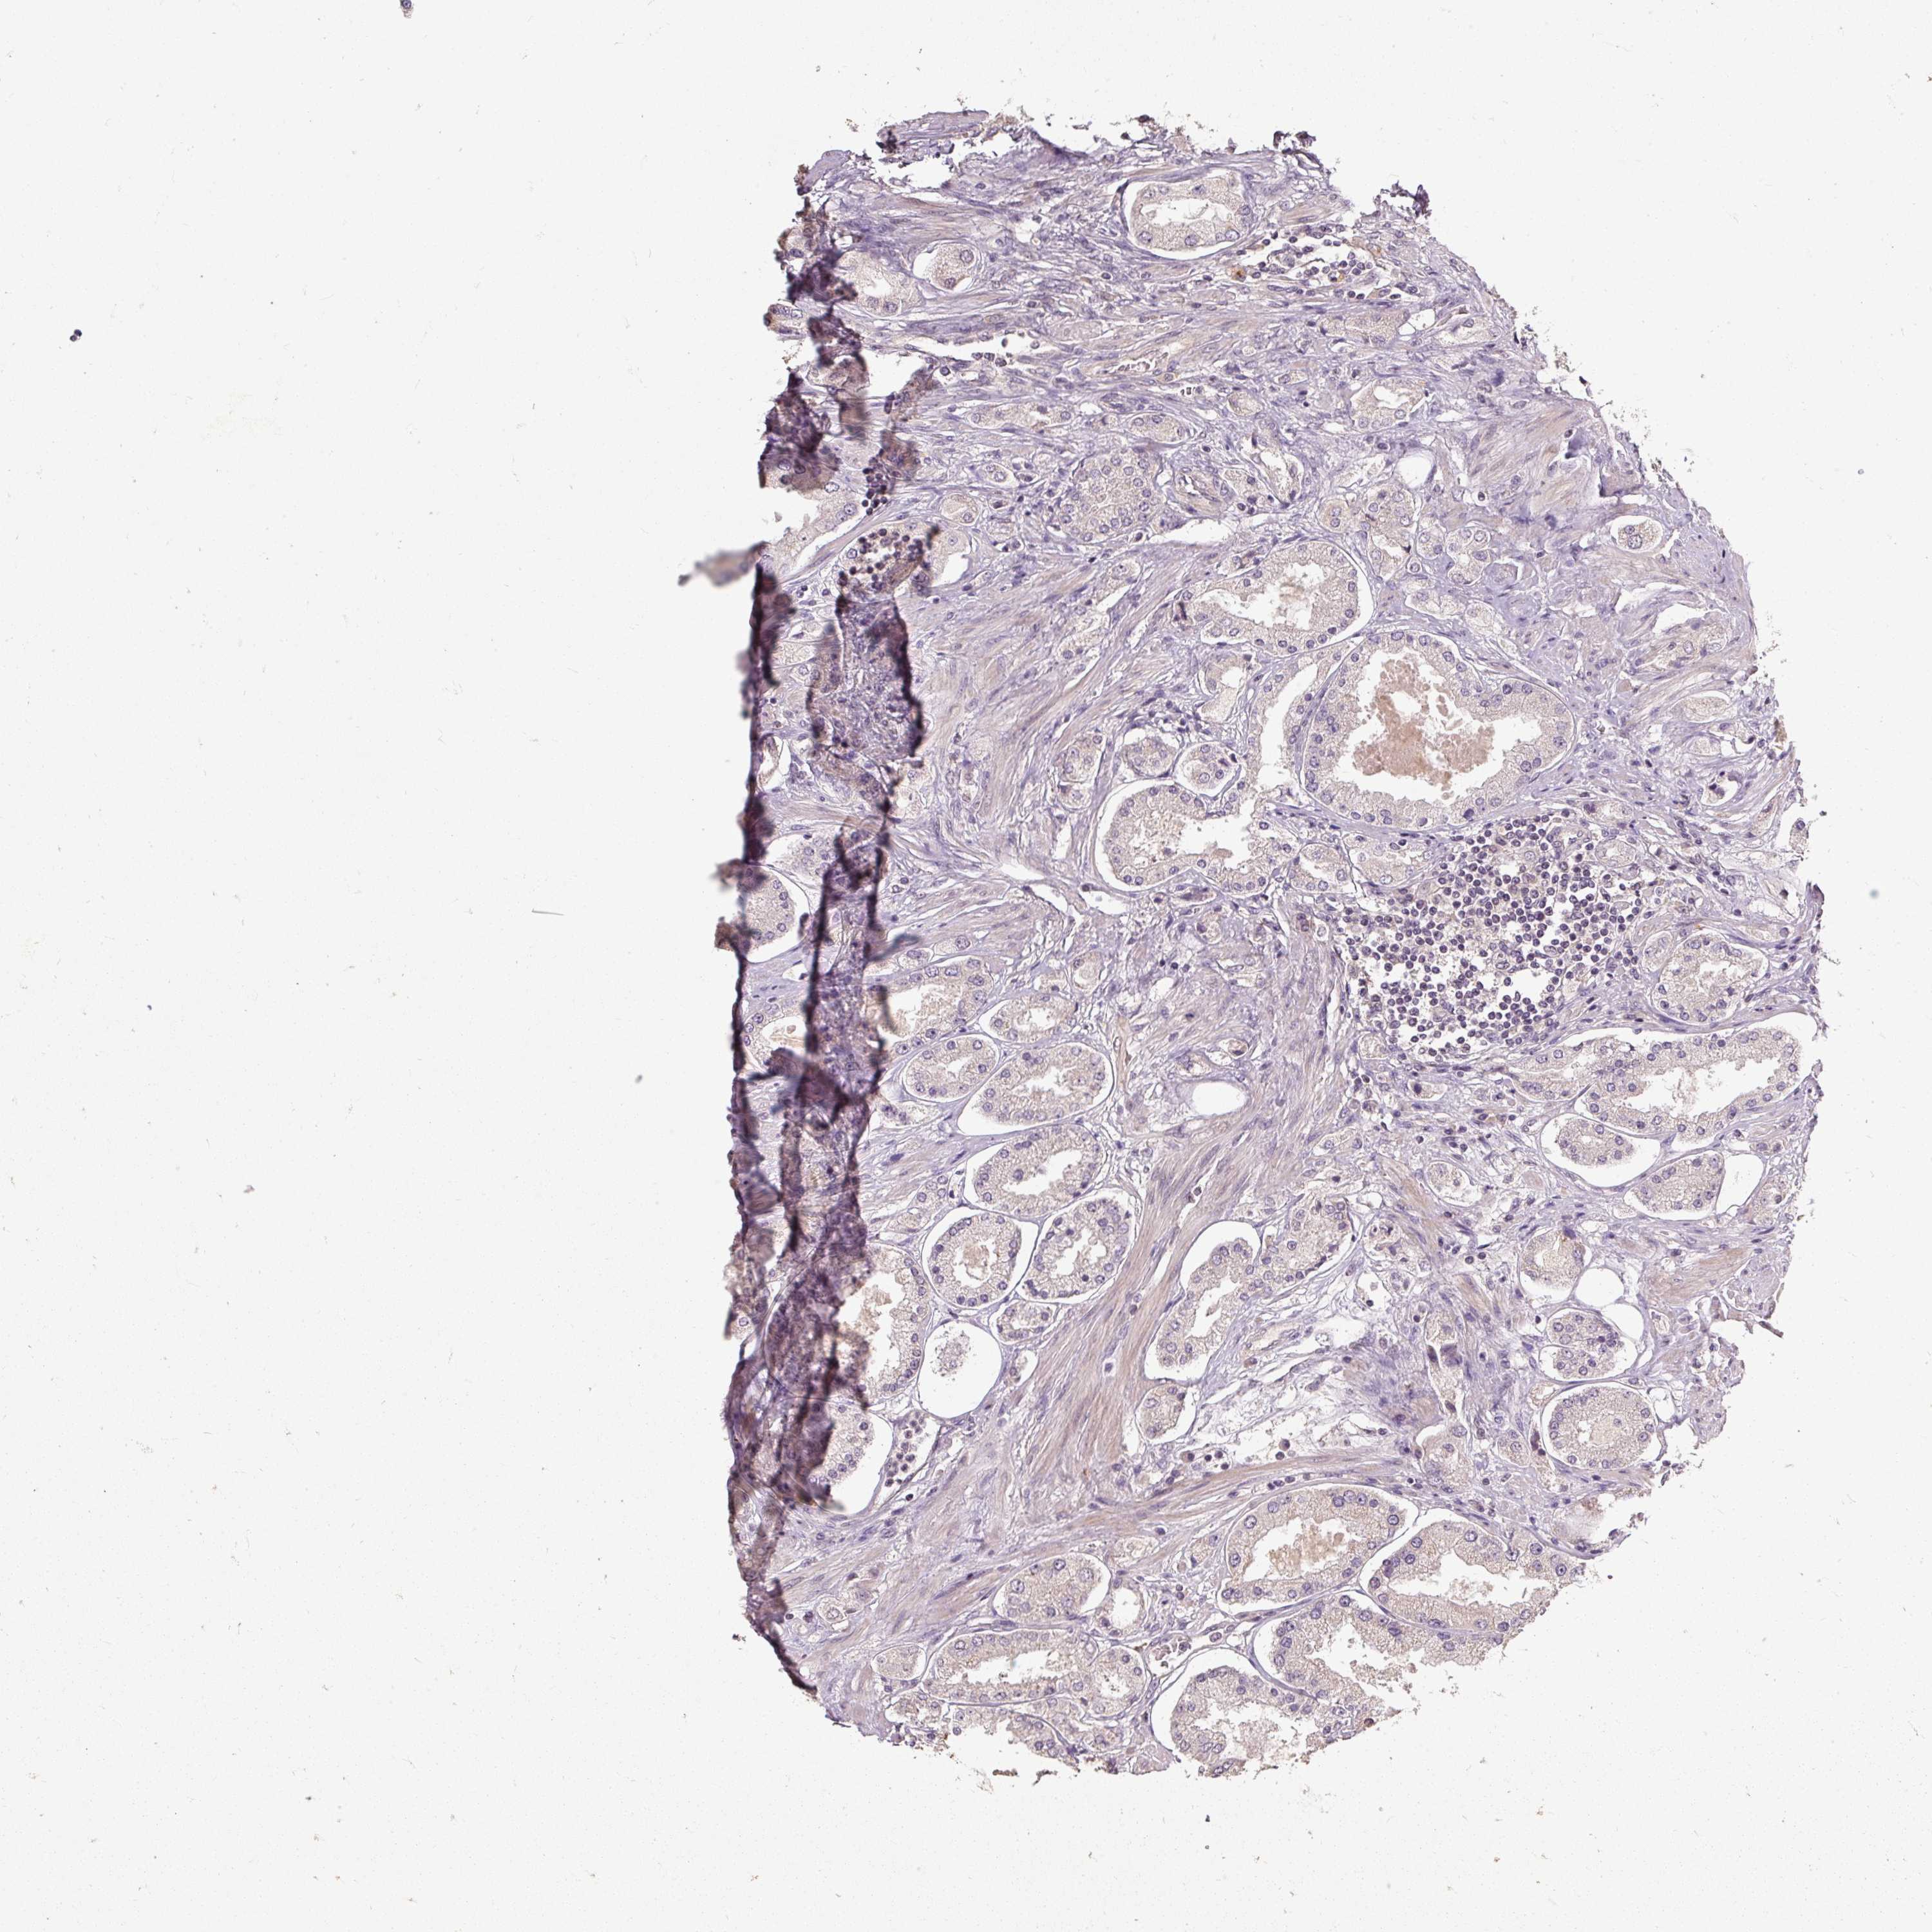

PROSTATE CANCER - Protein expressioni

A mouse-over function shows sample information and annotation data. Click on an image to view it in a full screen mode. Samples can be filtered based on level of antibody staining by selecting one or several of the following categories: high, medium, low and not detected. The assay and annotation is described here.

Note that samples used for immunohistochemistry by the Human Protein Atlas do not correspond to samples in the TCGA dataset.

Antibody stainingi

Antibody staining in the annotated cell types in the current human tissue is reported as not detected, low, medium, or high, based on conventional immunohistochemistry profiling in selected tissues. This score is based on the combination of the staining intensity and fraction of stained cells.

Each image is clickable and will lead to virtual microscopy that enables deeper exploration of all samples and also displays staining intensity scores, fraction scores and subcellular localization as well as patient and tissue information for each sample.

Antibody HPA055156

Staining

High

Medium

Low

Not detected

Intensity

Strong

Moderate

Weak

Negative

Quantity

>75%

75%-25%

<25%

None

Location

Nuclear

Cytoplasmic/membranous

Cytoplasmic/membranous,nuclear

Adenocarcinoma, High grade

Adenocarcinoma, NOS

Adenocarcinoma, Low grade